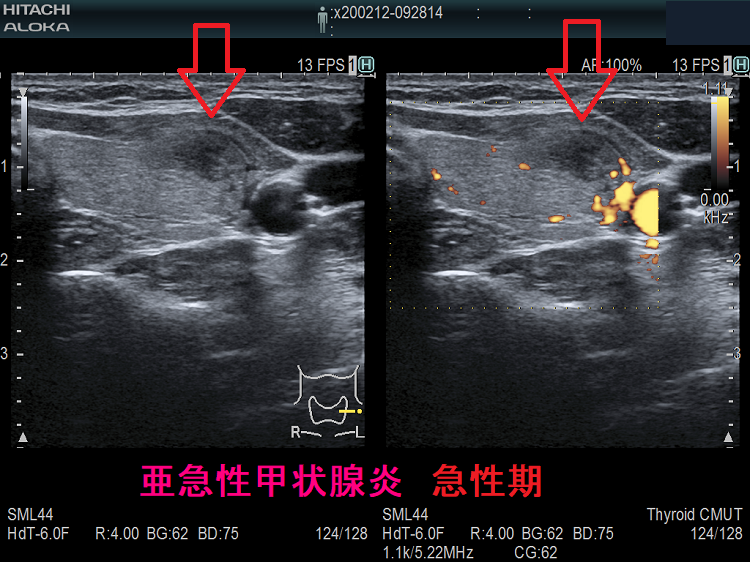

下は亜急性甲状腺炎の超音波(エコー)画像で、炎症の強い部分は黒く、エラストグラフィーでは青くなります。